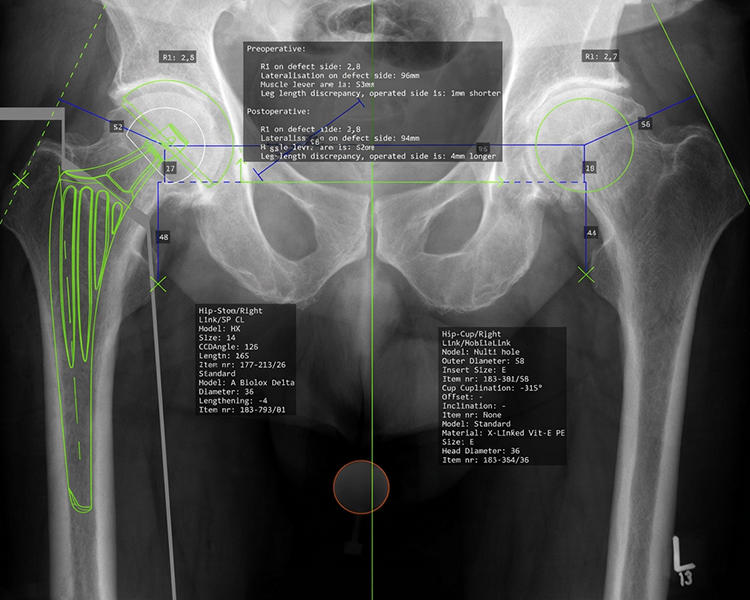

CAD-gestützte Planung

Nach meiner Überzeugung kann nicht jeder Patient mit einem einzigen Prothesenmodell erfolgreich versorgt werden. Daher arbeite ich seit vielen Jahren mit verschiedenen bewährten Prothesenmodellen, um nahezu jede individuelle Anatomie optimal abzubilden.

Nur durch diese maßgeschneiderte Auswahl können die Muskeln wieder in ihrer natürlichen Funktion arbeiten,  die Voraussetzung für schmerzfreies Gehen und bestmögliche Lebensqualität.

Die computergestützte (CAD) Planung ermöglicht es, jeden Eingriff präzise zu simulieren und die optimale Prothese für Ihre individuelle Anatomie auszuwählen, für maximale Präzision und langfristig erfolgreiche Ergebnisse.

computergestützte OP-Planung für optimale Ergebnisse:

• Patientenspezifische Anatomieanalyse

• Präzise Implantatauswahl & -positionierung

• Simulation von Offset, Beinlänge & Gelenkzentrum

• Biomechanisch optimierte Rekonstruktion